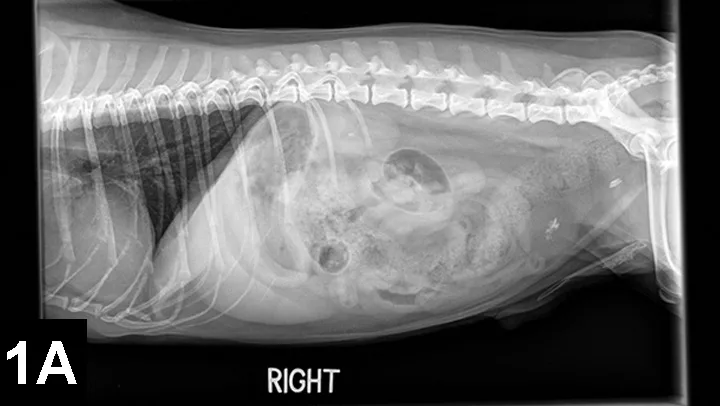

Figure 1A. Lateral radiograph of a 13-year-old, castrated shih tzu with multiple CaOx uroliths (kidneys, bladder, and urethra).

Older dogs and cats (8–12 years) are most commonly affected by CaOx uroliths, and concurrent urinary tract infection appears to be rare. CaOx uroliths are typically the most radioopaque of all uroliths and usually easily observed on plain film radiographs (Figures 1 and 2).